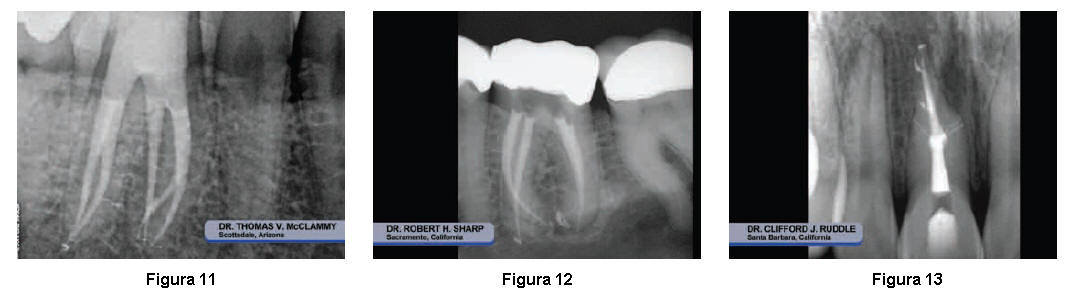

Sistemas

de conductos

limpios y

permeables,

proporcionan el éxito

de la

obturación

3D a largo plazo

(Figuras

11- 14).